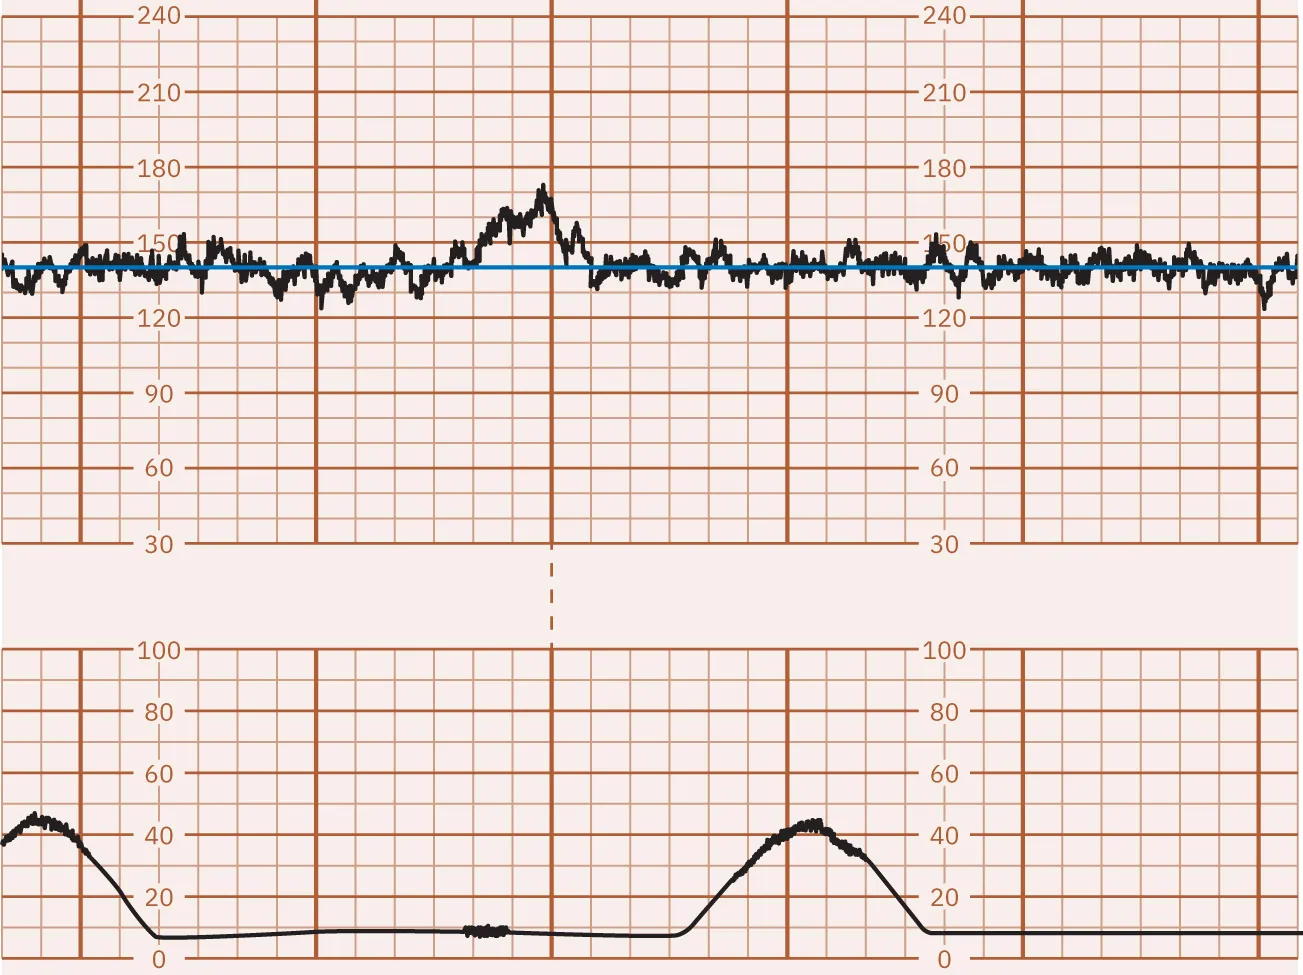

Basic Terminology Used to Interpret Contraction Patterns

Uterine contractions are monitored for frequency, intensity, and duration. As discussed in Chapter 15 Process of Labor and Birth, the frequency is how many minutes from the start of one contraction to the start of the next contraction. Intensity is the strength of the contraction. Duration is the number of seconds from the start to the end of a contraction.

As shown in Figure 16.15, the monitor graph is divided by darker or more prominent vertical lines to represent 1 minute of time and less prominent vertical lines showing 10-second intervals. The upper set of horizontal lines represents the fetal heart rate in beats per minute (bpm), usually in intervals of 10 bpm. The lower set of horizontal lines represents the intensity of the contractions in millimeters (mm) of mercury (Hg), in intervals of 5 to 10 mm Hg.

An image showing a fetal heart rate and uterine contraction monitoring graph. The top graph represents the fetal heart rate with a line oscillating around 120 beats per minute, marked by regular vertical red lines. The bottom graph shows uterine contractions with three bell-shaped curves aligning with the red lines above, and green lines indicating the start and end of contractions.

Figure 16.15 Fetal Heart Rate and Contraction Monitor Graph This monitor tracing shows the fetal heart rate baseline of 130. The contraction frequency is 2 to 3 minutes. The contraction duration is 45 to 70 seconds. The contraction intensity is 50 to 70 mm Hg. (attribution: Copyright Rice University, OpenStax, under CC BY 4.0 license)